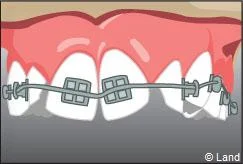

Il s’agit d’un appareil multi-attaches appelé communément « bagues ». Il permet de déplacer très précisément chaque dent. Chaque dent est équipée d’une attache appelée « bracket ». Les dents vont être mobilisées par l’utilisation de fil métallique dont l’alliage, la section, la forme sont déterminés par les différentes étapes du traitement. Ils seront insérés dans les attaches par le biais de ligatures élastiques, métalliques ou d’un mini-clip. Les « brackets » utilisés chez les adolescents sont la plupart du temps métalliques mais ils peuvent être remplacés avantageusement par des éléments transparents ou de la couleur des dents.